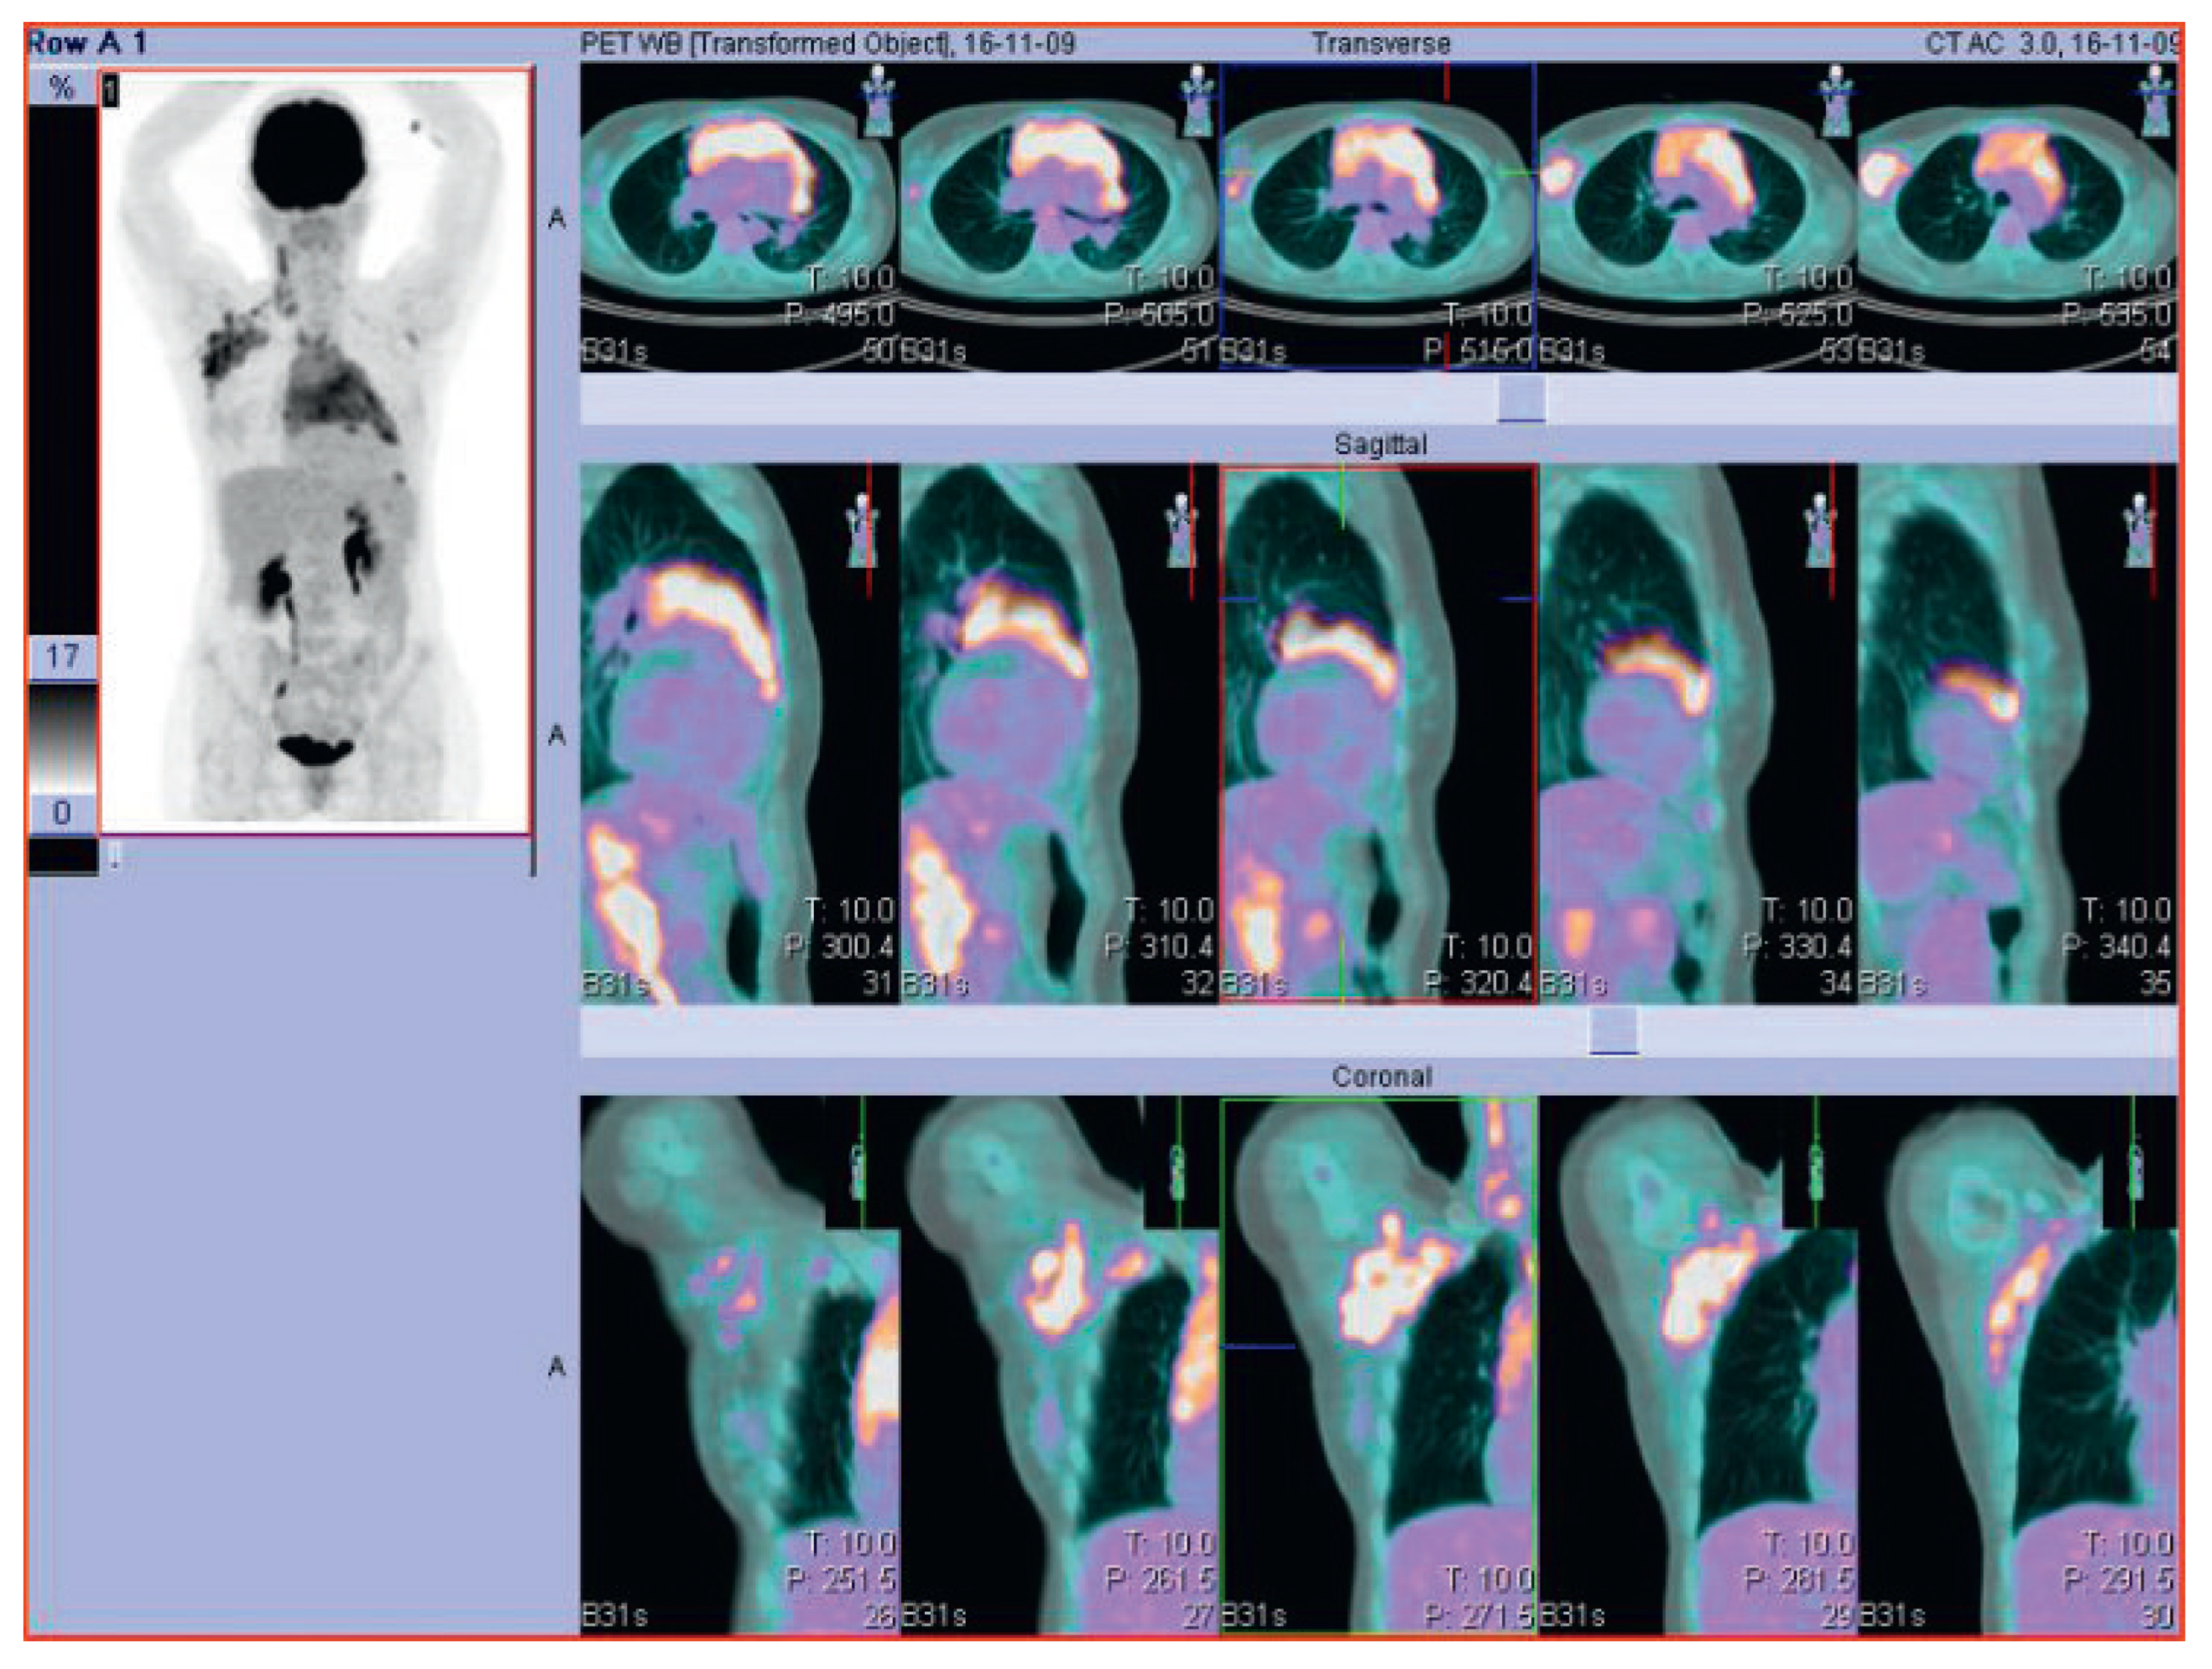

Cardiac complications in a patient with Hodgkin lymphoma—a case report

Figure 1. PET-CT scan of a 47-year old woman with Hodgkin lymphoma at the first diagnosis.